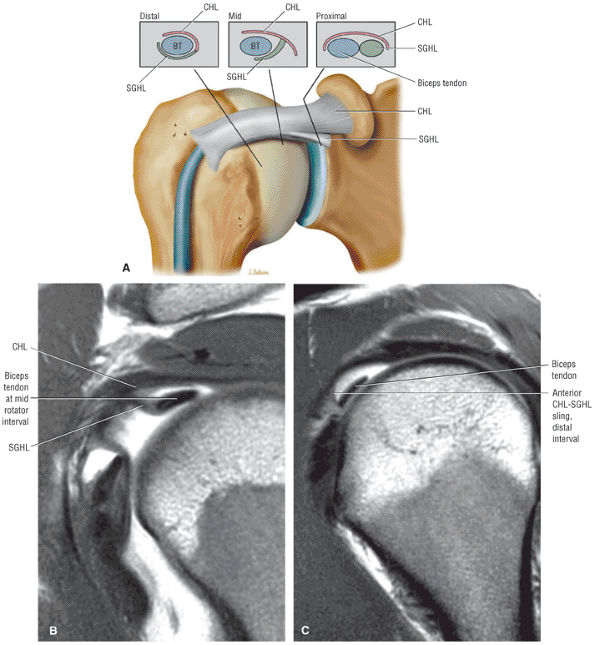

FIGURE 8.94 ● (A) The biceps pulley complex is sectioned in the sagittal plane at the level of the proximal, middle, and distal rotator cuff interval. The confluence of the CHL and SGHL occurs at the middle and distal aspects of the rotator interval. A T-shaped junction is formed between the SGHL and CHL at the mid-interval, superior to the humeral head. An anterior U-shaped sling is shown at the distal interval at the entrance to the bicipital groove. (B) An anterior coronal FS PD FSE image demonstrates the biceps tendon contained between the CHL and SGHL components of the biceps pulley.

FIGURE 8.95 ● Sagittal MR arthrograms. (A) The anterior biceps sling is formed by the confluence of the CHL and SGHL anterior to the LHBT. (B, C) The T-shaped junction of the SGHL and CHL at the midportion of the rotator cuff interval.